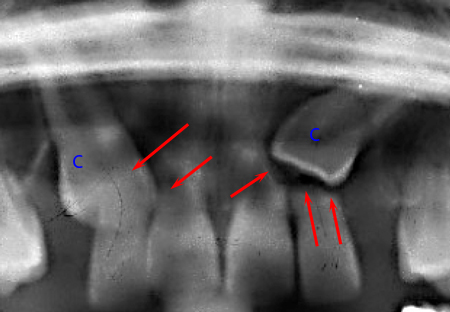

This series of X-rays shows well the problems that can create inflammation or infection to the apex (tip) of the root of a primary tooth (green “C” letter). The white arrows define enlarged follicular envelopes around the permanent canine crown (blue “C”).

The primary canines (green “C”) received a pulpotomy (partial removal of the pulp) because of a cavity or to reduce the sensitivity of the primary tooth when a cut is made through enamel and dentin. This results in chronic inflammation of the nerve and at the apex; this inflammation will be defined by an apical granuloma. This granuloma irritates the follicular envelope surrounding the permanent canine crown (blue “C” letter) and the granuloma becomes an obstacle in front of the permanent tooth. The tooth path of eruption is deflected. Therefore, a potential cause to the development of a follicular cyst would be chronic inflammation of the apical granuloma. (Becker, A., The orthodontic treatment of impacted teeth 2e ed.Thieme 2007, p.97 & 240.)